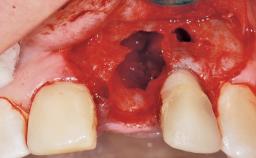

A 30-year-old female patient was referred to the office for the treatment of tooth 11. Her chief concern at the initial visit was to inquire, “Why is my tooth pink?” Upon clinical examination, it was determined that tooth 11 had a previous history of trauma and that the clinical crown had become noticeably pink in color as a result of internal resorption. This diagnosis was confirmed radiographically, indicating a large radiolucency involving the central and distal portions of the clinical crown. It was determined that restoration of this tooth was not possible, and that extraction was indicated. The presence of a mid-line diastema, which the patient wanted to reproduce, directed the treatment plan for tooth replacement utilizing a dental implant.

Soft Tissue Anatomy Intact Defective

Bone Volume Horizontally and vertically sufficient Horizontally deficient Deficient vertically or deficient vertically AND horizontally

Socket Integrity Sufficient, with intact bone walls

Bone Volume Sufficient, with intact walls